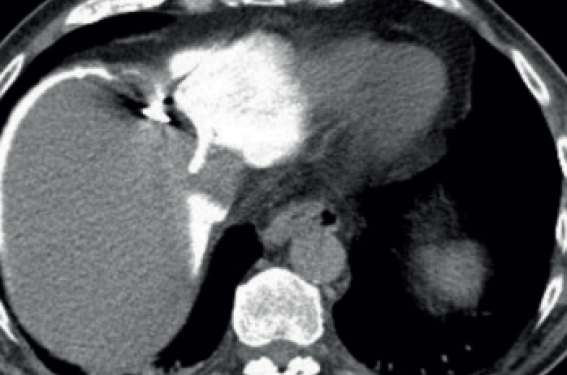

Faut-il protéger le diaphragme lors d’une thermoablation percutanée de tumeur hépatique paradiaphragmatique ?

La thermoablation percutanée hépatique à proximité du diaphragme Les complications des traitements thermiques sont rares, mais potentiellement graves dans le cas où l’hyperthermie locale diffuse accidentellement dans des structures adjacentes à la zone de thermoablation comme l’arbre biliaire...